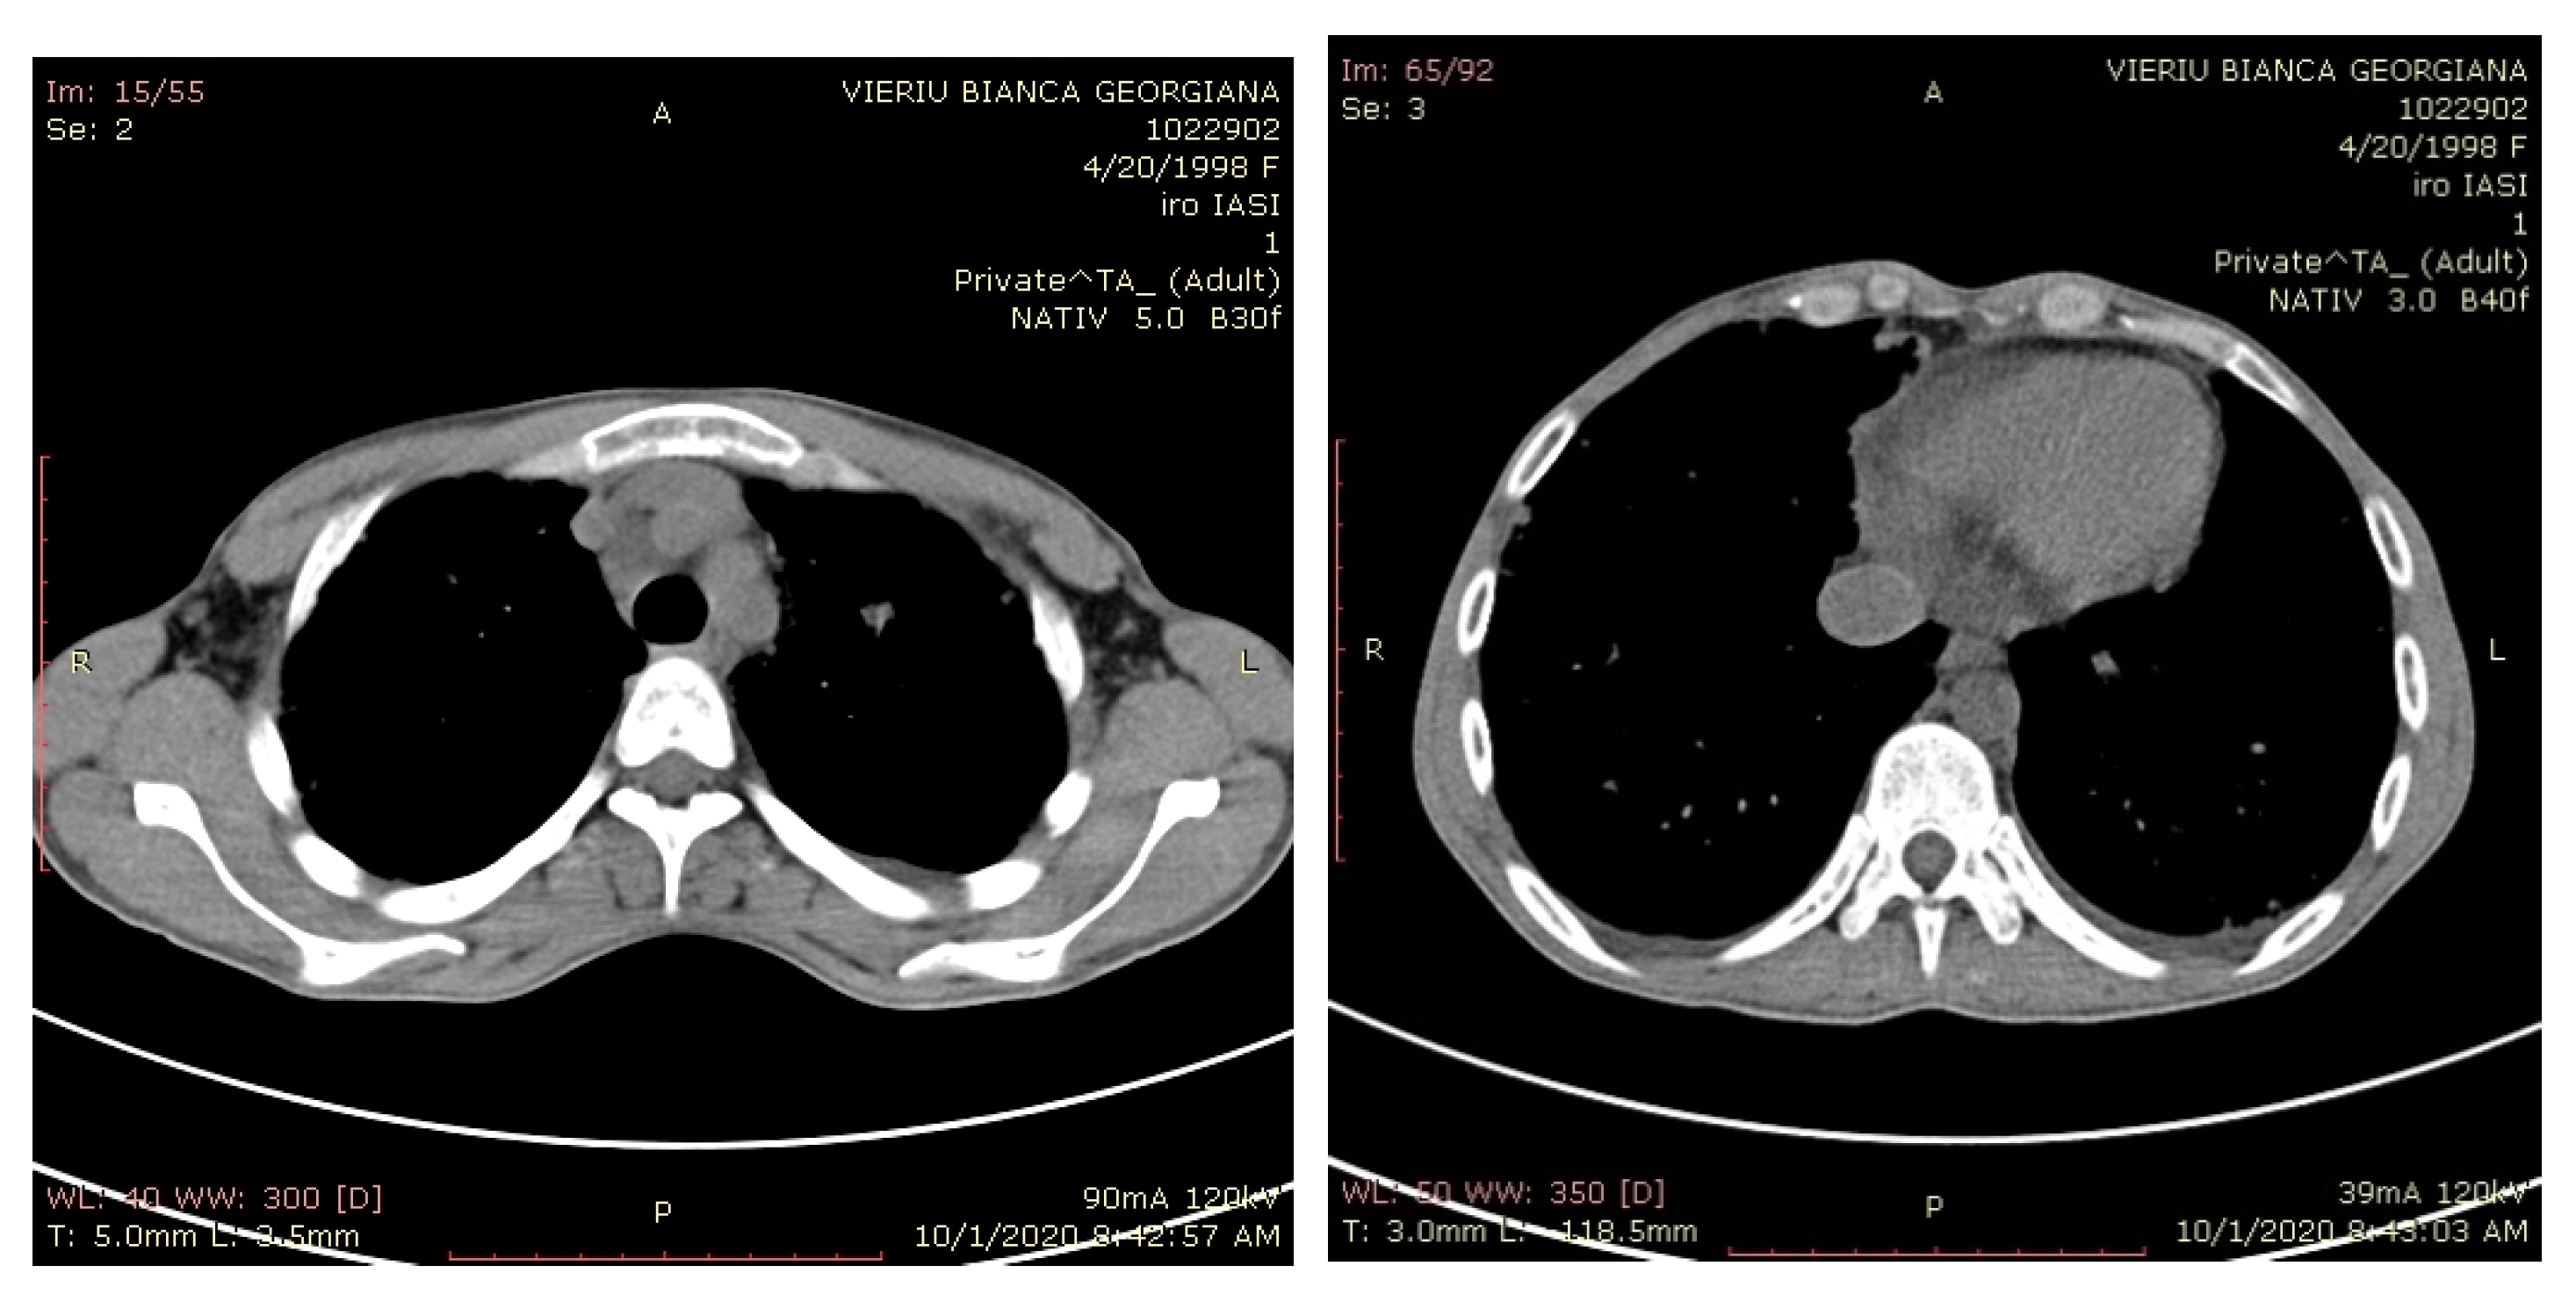

2. Case Presentation